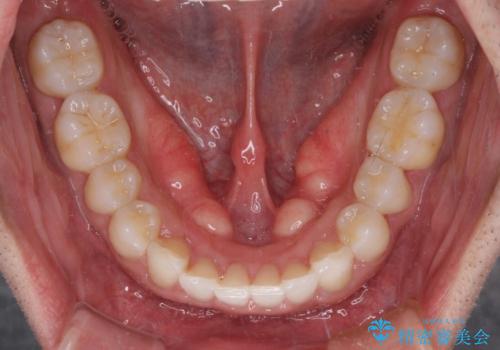

- 口の閉じにくさを気にして来院された患者様です。

患者様と相談の上、横顔の印象から抜歯矯正は必要ないと判断し、IPR(歯と歯の間)並びに歯列全体の後方移動により口元の突出感の改善することとしました。

しっかりと装着時間を守り、ゴムかけも徹底していただいたので、思いの外口元を引っ込めることができました。

これ以上の改善を望まれましたが、非抜歯矯正でこれ以上口元を引っ込めると食いしばりすやすい咬合となるため、この歯列で終了としました。